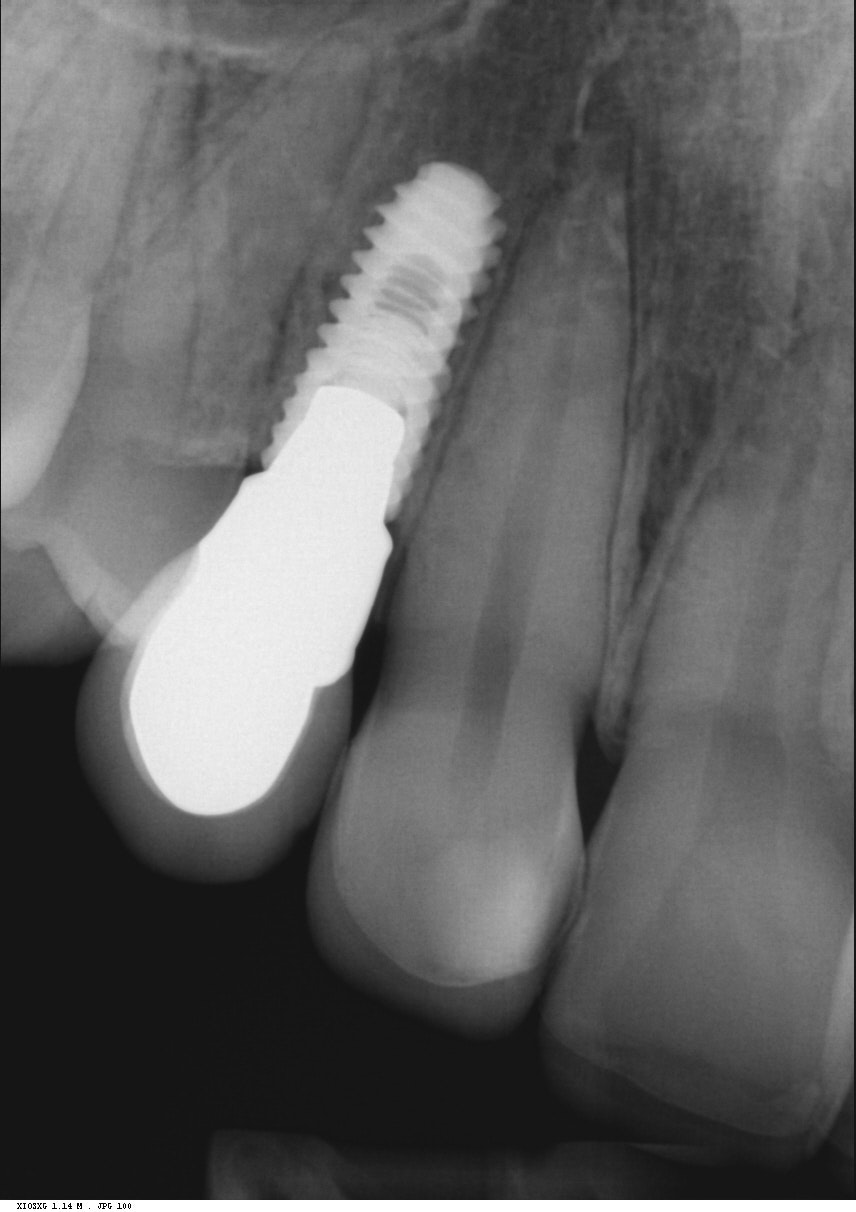

Implantit paikoillaan 1/3

Implantit paikoillaan 2/3

Implantit paikoillaan 3/3